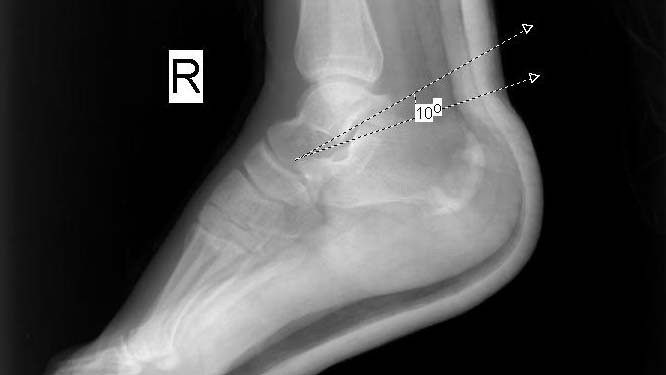

Böhler açısı kalkaneus fraktürü